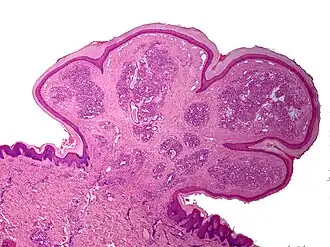

Un estudio ha sugerido una correlación entre los granulomas piógenos y la seropositividad a Bartonella[6]. Sin embargo, esta asociación ha sido cuestionada por otros[7]. La apariencia microscópica de un granuloma piógeno consiste en tejido de granulación altamente vascularizado, hay inflamación presente. La lesión puede tener un carácter fibroso si es más antigua y la superficie puede tener ulceraciones. Los granulomas piógenos rara vez aparecen en la conjuntiva, la córnea o el tejido conjuntivo del ojo después de un traumatismo local menor.

Un examen histopatológico de un granuloma piógeno mostraría múltiples capilares (debido a la naturaleza vascular del tumor), neutrófilos y tejido necrótico.